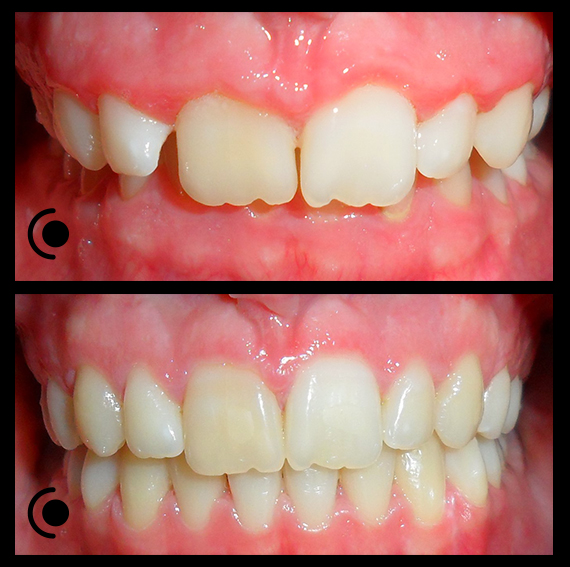

O našoj kvaliteti najbolje govore naši rezultati!

Centar za ortodonciju Petra Džapo